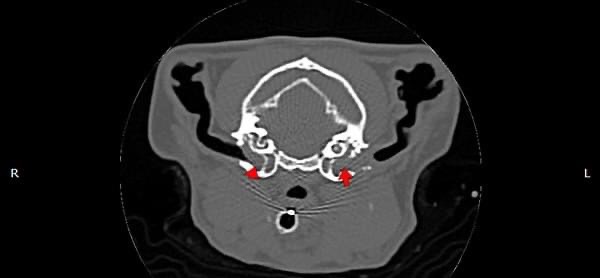

• 狗狗 車禍 骨盆骨折

狗狗 車禍 骨盆骨折